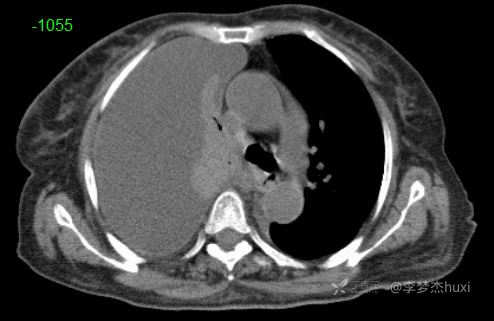

女性78岁,右侧满罐胸水,你绞尽脑汁也想不到的原因

体格检查:T:36.5℃;P:96次/分;R:20次/分;Bp:100/55mmHg,神清,呼吸平稳,浅表淋巴结不大,重度贫血貌,左肺叩清音,右肺叩浊音,右肺呼吸音消失,左肺呼吸音低,未闻及明显啰音,心率96次/分,律齐,无杂音。腹部平坦,软,全腹无压痛,无反跳痛及肌紧张,肝脾肋下未触及,双下肢水肿。

临床诊断:右侧胸腔积液